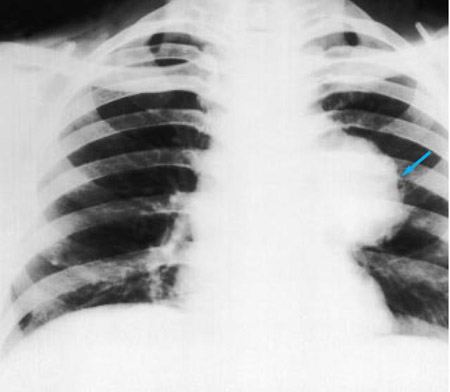

Chest x-ray showing left hilar carcinoma (arrow)

From: E. Dick, Student BMJ. 2000;8:358-360